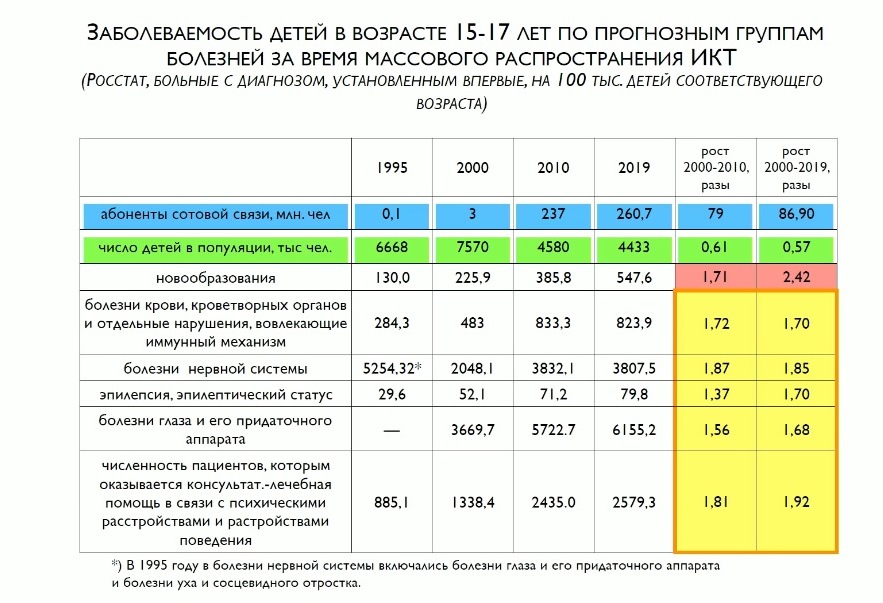

Мы работаем с данными Росстата – у них получается, что уже с трех лет дети являются активными пользователями гаджетов. Прежде всего – мобильных телефонов. ЭМП оказывают комплексное действие на здоровье детей. Мы видим ужасающие цифры за 20 лет внедрения цифровой среды – здесь кратный рост заболеваемости по всем возрастным группам. То есть эта частная цифровизация начинает подрывать сами основы существования общества.

Что касается роста новообразований у детей – могу сказать, что эпидемии нет, но рост числа опухолей совершенно четко наблюдается с момента начала пользования населения гаджетами. Это около 500 случаев в год – не очень много с точки зрения общей статистики, но корреляция видна четко. И нет ни одного серьезного исследования, которое бы говорило, что действия комплекса возникающих факторов – от ЭМИ до оптики, зрительной и двигательной нагрузки – что все это безопасно и не вредно для детей.